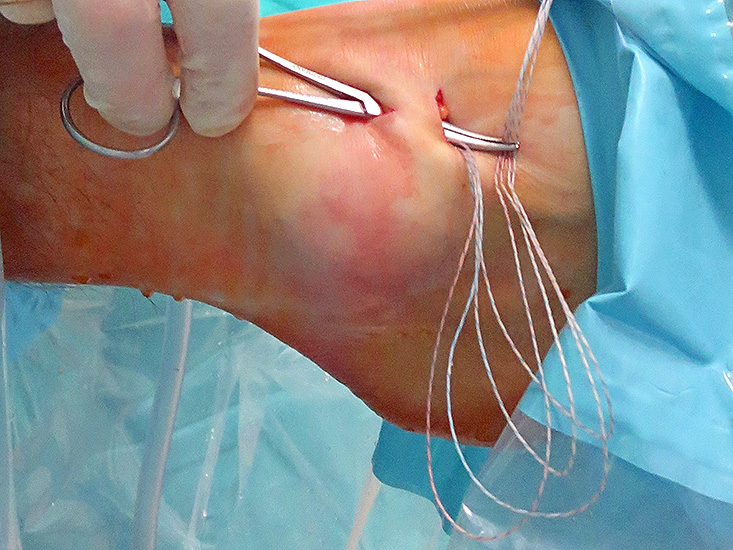

- Arthroskopisches Fadenholinstrument (Abbildung 1) oder eine gebogene kanülierte Ahle mit einer Drahtschlaufe (Abbildung 2).

- Läsion der N. Äste des N. peroneus superficialis (N. cutaneus dorsalis medialis et intermedius): siehe oben. Der N. cutaneus dorsalis medialis ist bei schlanken Patienten bei forcierter Plantarflexions- und Inversionsstellung des Fußes oftmals gut unter Haut zu palpieren. Befindet sich das Arthroskop bereits über das anteromediale Portal im Gelenk, kann durch die Ausrichtung der Lichtquelle nach ventral der Verlauf der Nerven mittels Diaphanoskopie dargestellt werden. Der N. cutaneus dorsalis intermedius verläuft oftmals auf Höhe des distalen akzessorischen Zugangs und sollte daher sorgfältig dargestellt werden. Durch Einsetzen kleiner Langenbeck- oder Venenhaken während des gesamten Fadenmanagements bis einschließlich zur Fixation des Retinaculums kann eine Verletzung dieses Nervs vermieden werden.